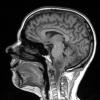

Astrocytoma, IDH-mutant, WHO Grade 2 (3)